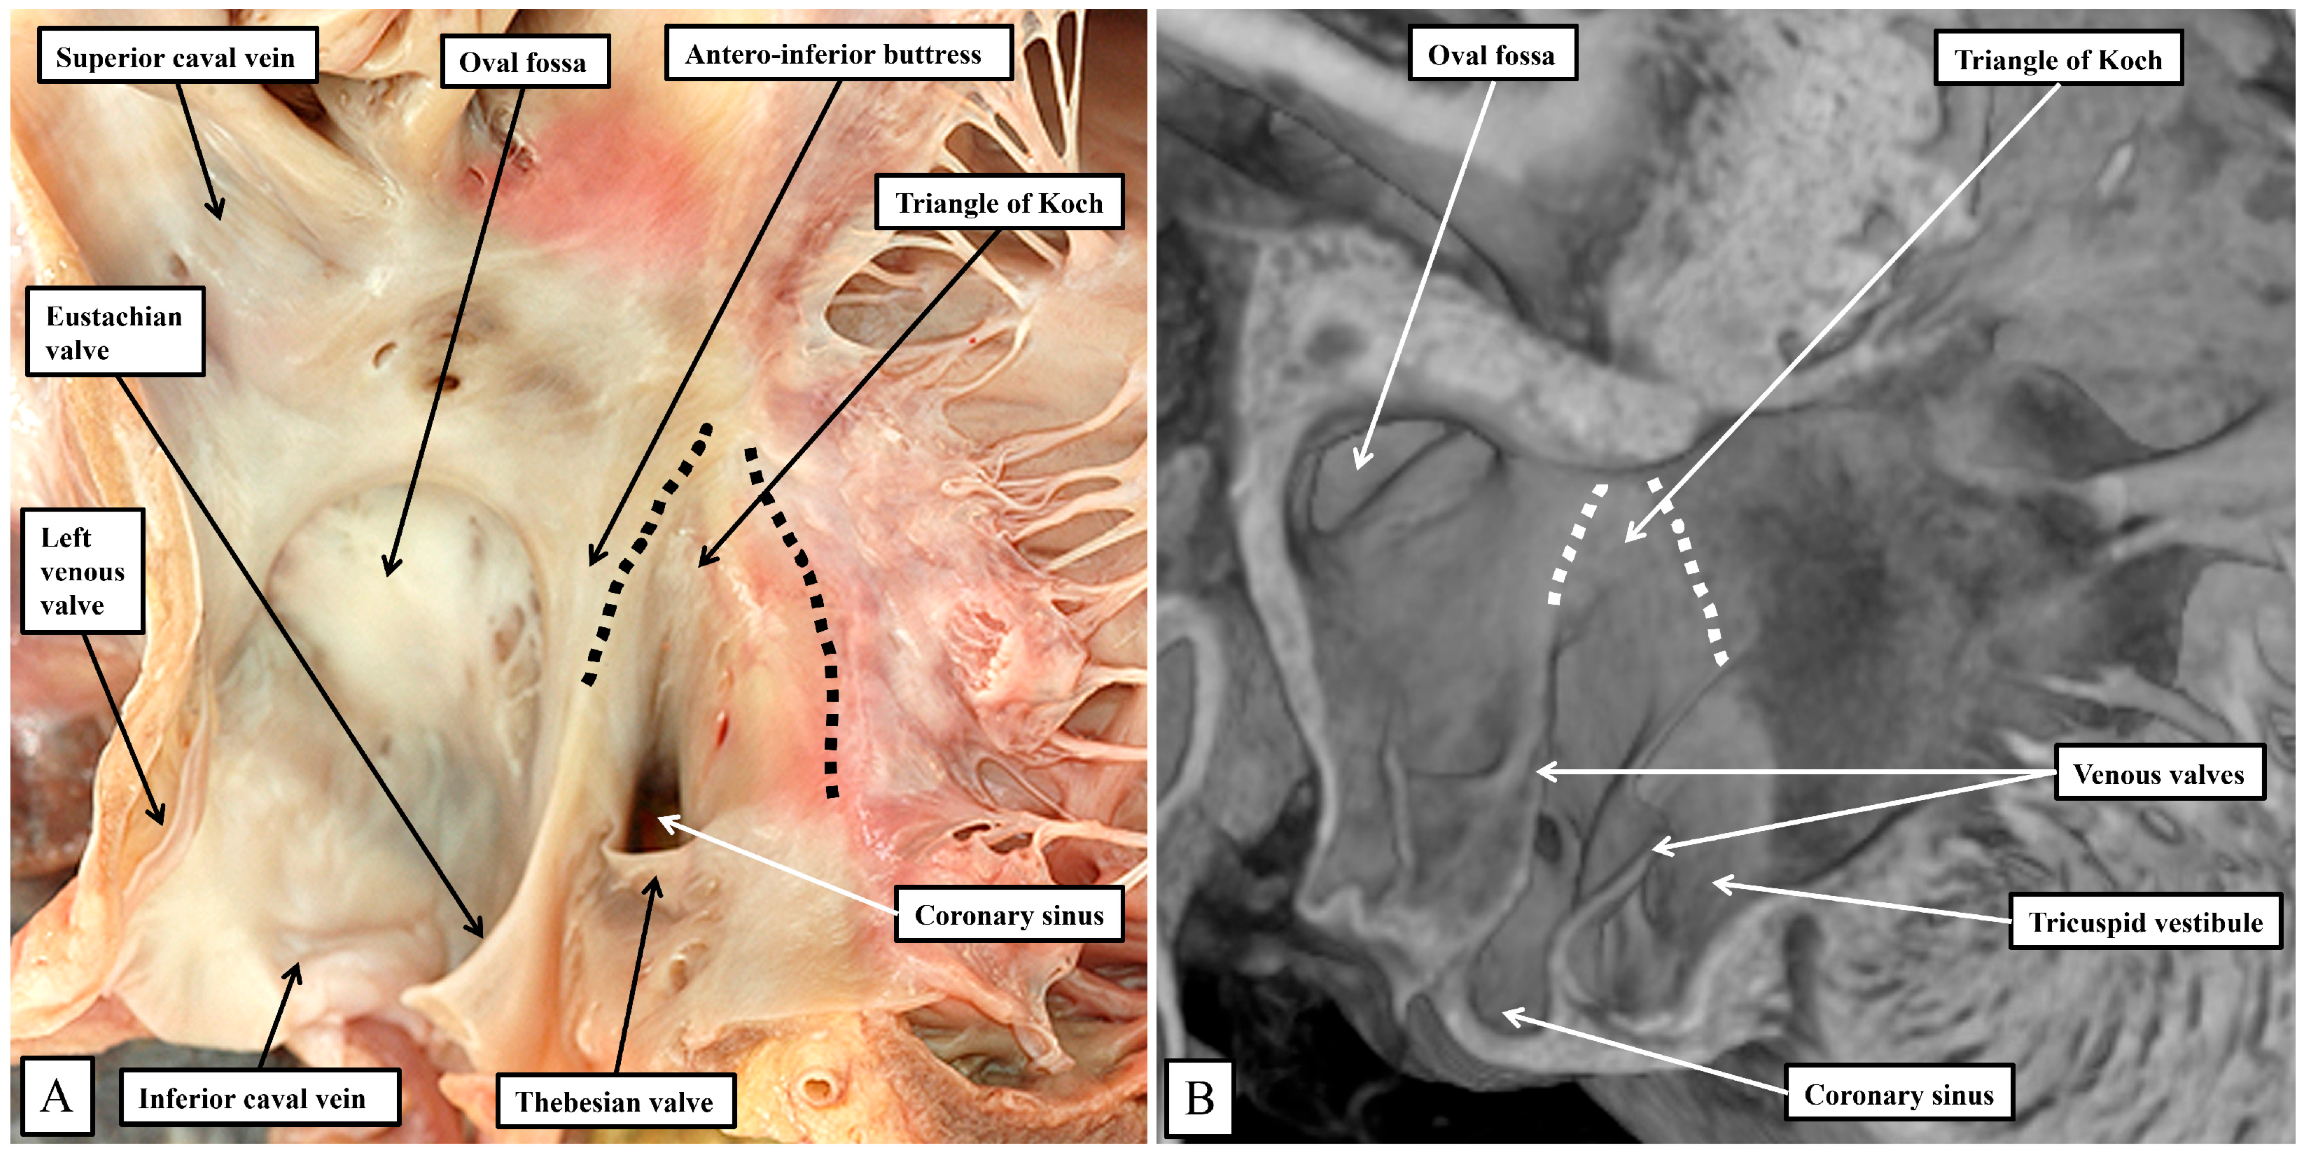

Removing the parietal walls of the right-sided chambers provides an en-face view of the septal atrioventricular junctions, and the septal surfaces of the morphologically right atrium and right ventricle (Figure 1A). A view of an episcopic dataset from a neonatal mouse prepared in a comparable fashion shows the similarities when the murine heart is positioned so as to parallel the human heart as viewed in an attitudinally appropriate fashion (Figure 1B).

As is shown in the photographs, when viewed attitudinally, the features are comparable. There are, however, subtle differences which impact on the location of the components of the atrioventricular conduction axis. Perhaps the most significant difference is the presence of a persistent left superior caval vein in the murine heart. This channel opens inferiorly into the vestibular region of the right atrium through an enlarged orifice of the coronary sinus (Figure 1B). In the human heart, the coronary sinus opens much more superiorly within the cavity of the right atrium (Figure 1A). The superior and inferior caval veins enter the systemic venous sinus in a comparable fashion in both species, but the opening of the venous sinus to the morphological right atrium is more dorsal in the murine heart (Figure 1B). The junction between the venous sinus and the remainder of the atrium is then much more obvious in the murine heart since the venous valves are much better preserved, with obvious right and left venous valves coming together at a superior commissure attached within the atrial appendage by the prominent pectinate muscle known as the septum spurium (Figure 1B). In the human heart, it is usually only parts of the right venous valve that persist. These remnants are the Eustachian valve, which partially guards the entrance of the inferior caval vein, and the Thebesian valve, which guards the opening of the coronary sinus (Figure 1A). The two valves come together at the area of the atrial wall separating the orifice of the coronary sinus from the oval fossa. Usually described as the sinus septum, the area is a fold between the walls of the inferior caval vein and the coronary sinus. The area of union between the valves then continues as a tendinous structure that runs within the antero-inferior buttress of the oval fossa. As we will describe, this fibrous entity, known as the tendon of Todaro, forms a boundary of the triangle of Koch, itself providing a landmark to the site of the atrial components of the conduction axis. The situation is more obvious in the murine heart since venous valves marking both the right and left borders of the systemic venous sinus remain subsequent to birth (Figure 1B). In the human heart, nonetheless, with careful examination, it is sometimes possible to recognize small remnants of the left venous valve plastered onto the septal surface of the oval fossa and its surrounds. In the murine heart, the right and left venous valves form a tunnel that directs the flow from the inferior caval vein toward the oval fossa. The superior extension of both valves into the area between the coronary sinus and the oval fossa is also much more marked, with a triangular area such as described initially by Koch also to be found in the mouse heart (see below). There are also subtle differences in the arrangement of the oval fossa between the species. In the human heart, the superior rim of the fossa is an obvious infolding between the attachments of the superior caval vein to the right atrium, and the right pulmonary veins to the left atrium. This arrangement is not found in the murine heart since the pulmonary veins open to the morphologically left atrium through a common orifice located inferiorly rather than superiorly, with a fold present in the dorsal wall, rather than superiorly as found in the human heart. The flap valve of the oval fossa in the murine heart closes against the roof of the atrium, such that the dorsal fold is not obvious (Figure 2A), rather than directly against the superior interatrial fold as is the case in the human heart.

Figure 1. (A) shows the features of the morphologically right atrium and ventricle of the human heart, having removed their parietal walls, with the heart shown in an attitudinally appropriate position. (B) shows an image from an episcopic dataset from a neonatal mouse heart sectioned to parallel the arrangement as seen in (A). The features are basically the same, although, as explained in the text, there are subtle differences that impinge on the arrangement of the atrioventricular conduction axis.